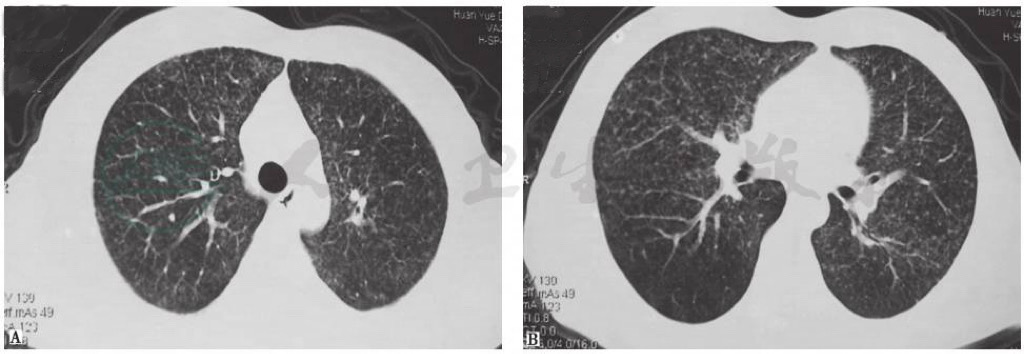

17个月前胸部CT见双肺弥漫性小结节(图1)。

图1 17个月前胸部CT表现